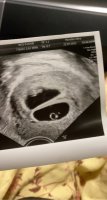

Alt såg bra ut, og var komt like langt som forventetEr så letta! 7+4 og hjerterytme på ca 155

Så deilig! GratulererAlt såg bra ut, og var komt like langt som forventetEr så letta! 7+4 og hjerterytme på ca 155

Gratulerer!Alt såg bra ut, og var komt like langt som forventetEr så letta! 7+4 og hjerterytme på ca 155